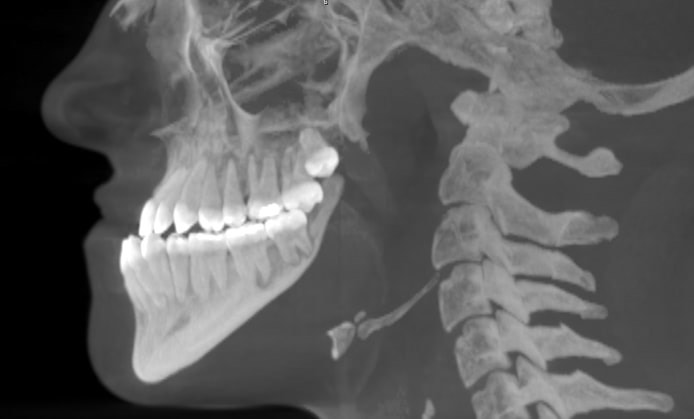

140. На рис. представлена аномалия окклюзии зубных рядов ___________ окклюзия в сочетании с ______ резцовой дизокклюзией

140. На рис. представлена аномалия окклюзии зубных рядов ___________ окклюзия в сочетании с ______ резцовой дизокклюзией 2